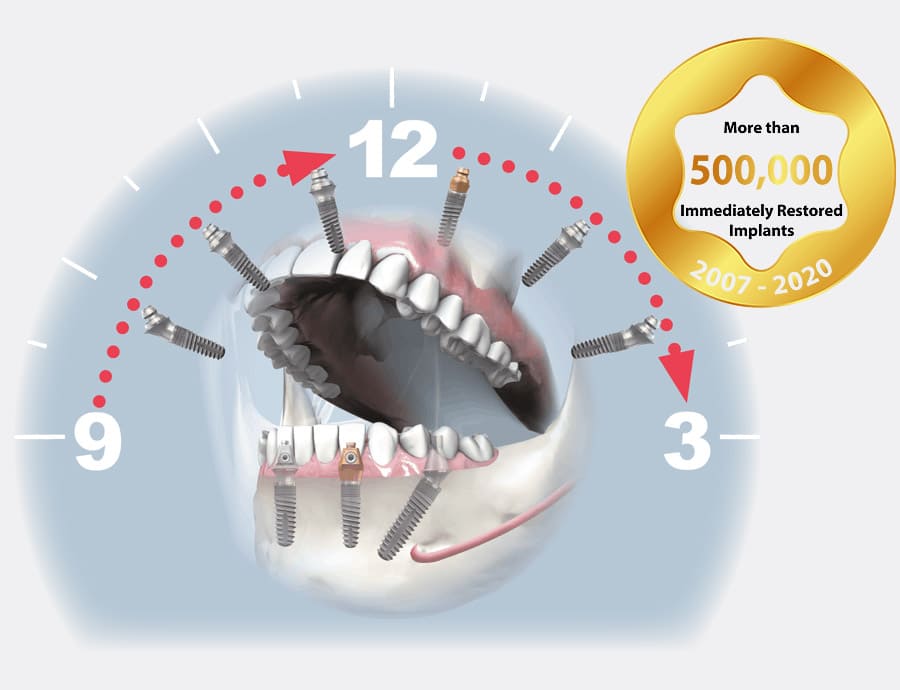

Fast & Fixed implant tekniği, tam dişsiz hastalarda belirlenen açılara göre yerleştirilen ; dört adet dental implant üzerine diş protezinin sabitlenmesini sağlayan bir yöntemdir.

Tam dişsiz hastalara aynı gün, tek bir cerrahi işlem ile geçici veya daimi sabit diş protezi yapılabilme imkânı sunar.

Geçici yapıldığı durumlarda hasta implantın kemikle osteoentegre olma sürecinde hastaya konfor sağlar.

Sonrasında daimi protezi yapılır.

Gerekli görüldüğünde implant sayısı 5 veya 6’ya çıkarılabilir.